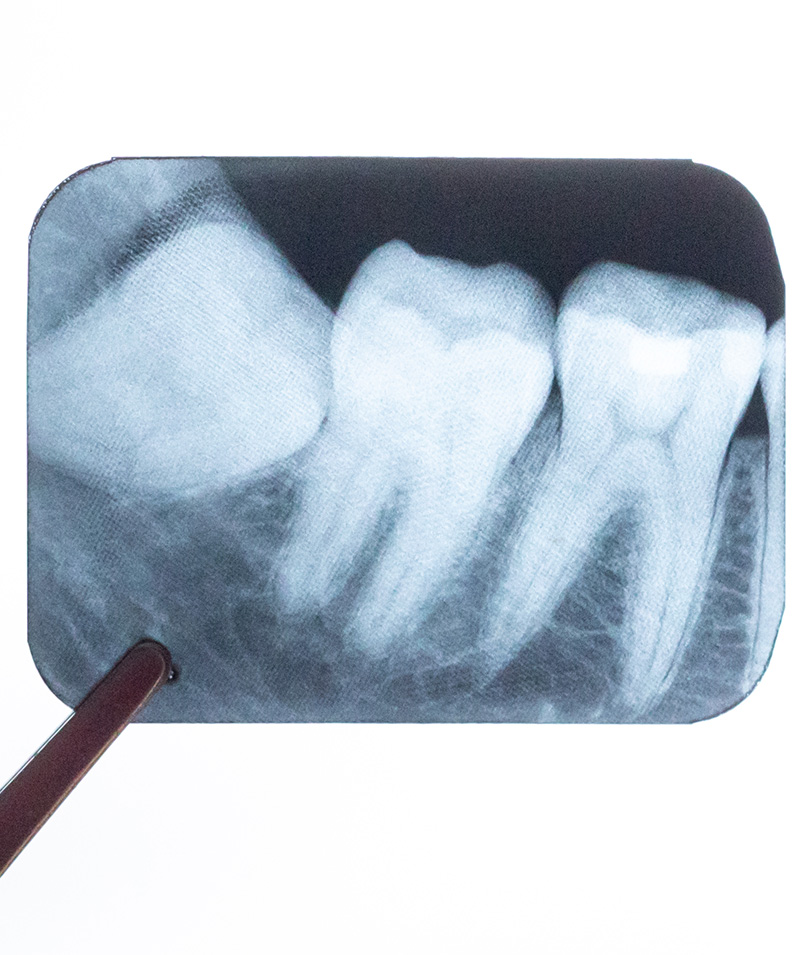

親知らずの抜歯や精密根管治療にも

複雑な方向に埋まっている親知らずの抜歯や、歯の根が細かく枝分かれしていたり湾曲していたりする、難易度の高い根管治療(歯の神経の治療)においても、CTは大きな力を発揮します。 事前に歯や神経、周囲の骨の正確な状態を立体的に把握することで、手術時間の短縮や術後の痛み・腫れといった不快症状のリスクを軽減することに繋がります。